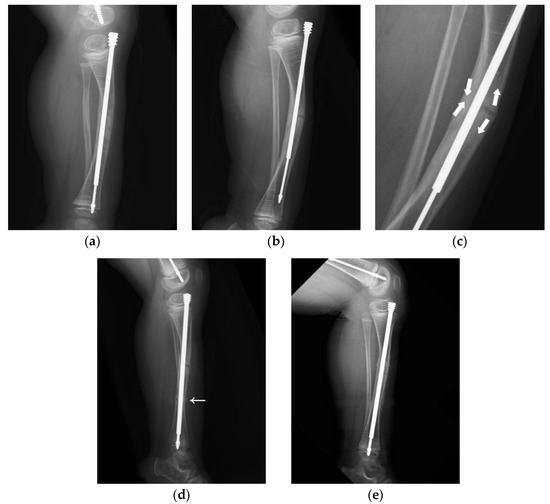

Another of our cases involved a boy who received double osteotomies and fixation with an FD nail in his right femur at the age of 1.5 years (Figure 3). The proximal osteotomy segment was too small to align and the greater trochanter had not ossified, so it was difficult to find the most suitable entry point under the c-arm (Figure 3a). During follow-up, we found that the female thread had become much more distal and anterior (Figure 3b). In the following revision, due to concerns over damaging the apophysis of the femur and iatrogenic greater trochanter epiphysiodesis, with resulting sequela of valgus deformity, insufficient depth of the female component may have occurred, resulting in its proximal protrusion (Figure 3c,d). The importance of the entry point and adequate purchase of the proximal femur cannot be over-emphasized (Figure 3e).

Figure 3. Anteroposterior (AP) view radiograph of the femur of a 1.5-year-old male post FD nail implantation. (a) The boy received double osteotomies and fixation with an FD nail in the right femur. The proximal fragment was extremely small and difficult to control, and the greater trochanter had not yet been ossified, so it was a huge challenge to find the most suitable entry point under the c-arm. We can see the entry point was anterior to the true position of the greater trochanter. (b) During regular follow-up, we found that the female thread had become much more distal and anterior with nail bending. (c) In the revision surgery, due to concerns over damaging the apophysis of the femur in order to avoid physis fusion and valgus deformity, we may have used insufficient depth of the female component. (d) During regular follow-up, we found proximal protrusion of the female component. (e) Good position and adequate purchase of the FD nail post revision surgery.